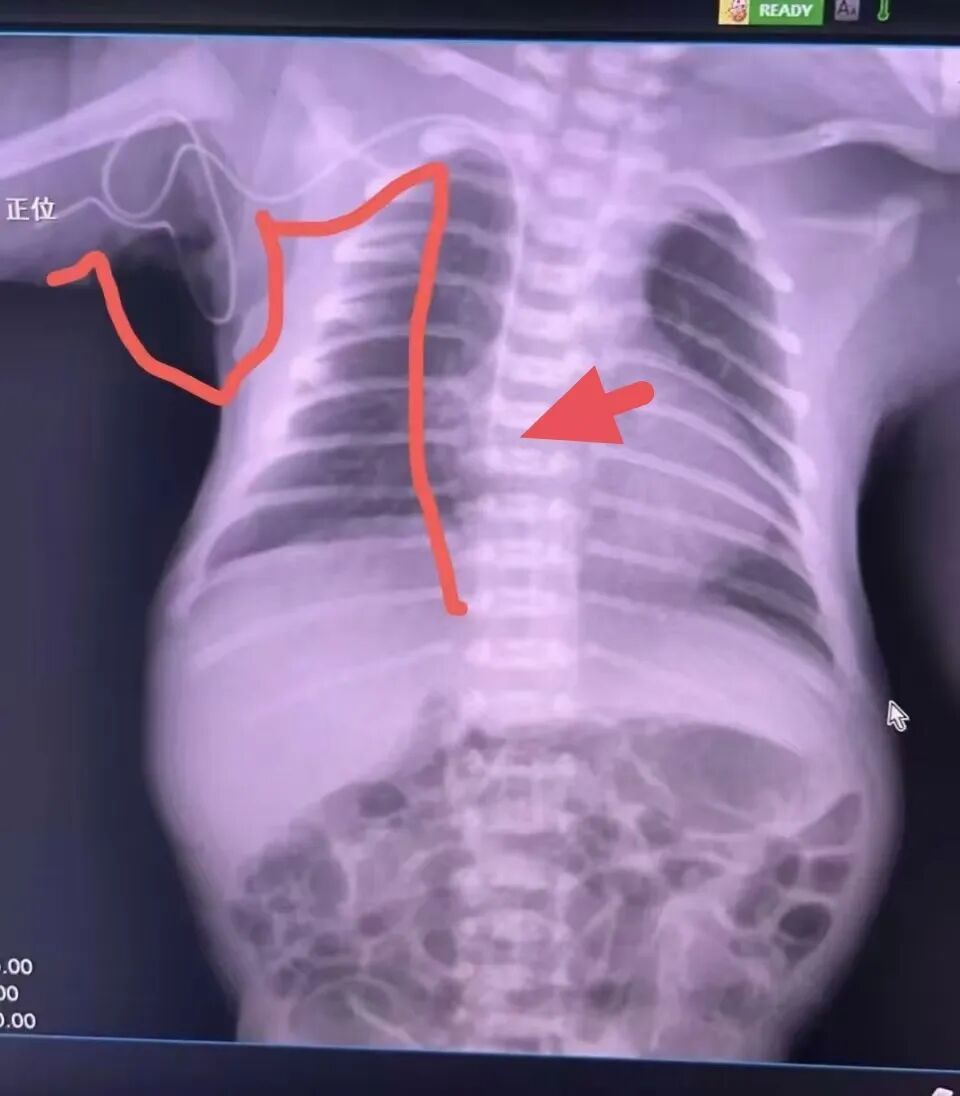

住院期间,为减去患儿穿刺痛苦同时降低并发症风险,新生儿重症监护室(NICU)护理团队在征得家属同意和对患儿的置管情况进行充分评估后,顺利为患儿开展新生儿PICC置管。术后PICC管道通畅,X线片显示导管末端位置准确。目前,在新生儿科医护团队的精心治疗和护理下,患儿已康复出院。

术后X线片